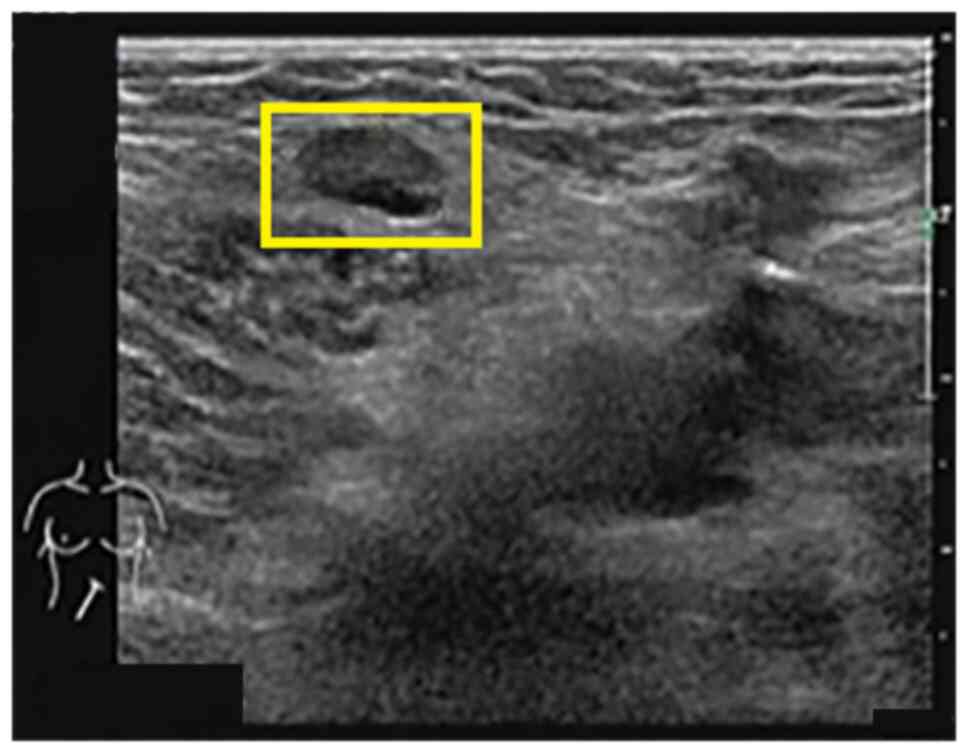

Laboratory investigation revealed the following: All enzymes representing liver and bile duct damage were elevated, including alanine aminotransferase (ALT) at 160 U/l (normal range, 9-50 U/l), aspartate aminotransferase (AST) at 142 U/l (normal range, 15-40 U/l), γ-glutamyl transpeptidase (GGT) at 742 U/l (normal range, 10-60 U/l) and alkaline phosphatase (ALP) at 467 U/l (normal range, 45-125 U/l). Direct bilirubin was slightly elevated to 8.3 µmol/l (normal range, 0-6.8 µmol/l), while albumin was severely reduced to 21.2 g/l (normal range, 40-55 g/l). Both amylase (AMY) and lipase (LPS) were increased to 120 U/l (normal range, 28-100 U/l) and 136.1 U/l (normal range, 13-60 U/l), respectively. The erythrocyte sedimentation rate and procalcitonin were also increased. The T cell spot test was positive. Except for elevated thyroid stimulating hormone (TSH) and anti-thyroglobulin antibody, there were no thyroid function abnormalities [free thyroid (FT) hormone 3, FT4 and anti-thyroid peroxidase antibody were all normal]. Both IgG and IgG4 were elevated to 85.44 g/l (normal range, 7-17 g/l) and 36.9 g/l (normal range, 0.03-2.01 g/l), respectively. Antinuclear antibody was positive. The antigen spectrum of autoimmune liver disease (e.g., anti-mitochondrial antibody-M2), anti-hepatorenal microsomes-1, anti-hepatocyte cytoplasmic antigen type 1 antibody, anti-soluble liver antigen/hepatopancreas antigen antibody, Ro-52, anti-promyelocytic leukemia protein antibody, nuclear autoantigen Sp-100, nuclear pore protein gp210 and 2-ketoacid dehydrogenase complex was negative. Other markers, such as C-reactive protein, complement, immunofixation electrophoresis, coagulation, hepatitis, viral antibody and tumor markers, were normal. The right intraocular pressure was 14 mmHg and the left intraocular pressure was 16 mmHg. The visual acuity of both eyes was 0.6. Defects in the right lower half, right upper half and left infratemporal region were detected in the 30-degree visual field. The synoptic muscle exhibited left inferior oblique paralysis. Orbital CT (Fig. 1) revealed a slightly thickened left inferior rectus muscle and paranasal sinusitis. Mild interstitial changes, slight chronic inflammation in both lungs, small nodules in both lungs, and mediastinal and bilateral axillary lymphadenopathy were detected on pulmonary CT. Prostate hypertrophy and calcification and lymphadenopathy around the bilateral internal iliac vessels were also observed on abdomen-enhanced CT. An ultrasound scan of the superficial lymph nodes revealed that the bilateral neck, bilateral supraclavicular fossa, bilateral subclavian fossa, submental, left axilla, right groin (grades 3-4, suspected malignancy) (Fig. 2), right axilla and left groin (grade 3) exhibited multiple enlarged lymph nodes. A hypoechoic mass was detected in the left submandibular gland. Rough echo of the liver parenchyma and increased elasticity of the liver (10.6 kpa) were observed in the abdominal ultrasound scan.

Figure 2

Ultrasound scan of the right groin displaying an enlarged lymph node (highlighted area; scale bar, 4 cm).